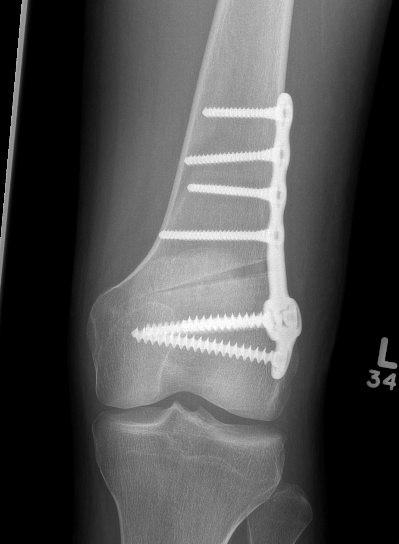

Distal femoral locking plate + bone graft

DFVO 3DFVO 2DFVO 3

DFVO 1DFVO 2